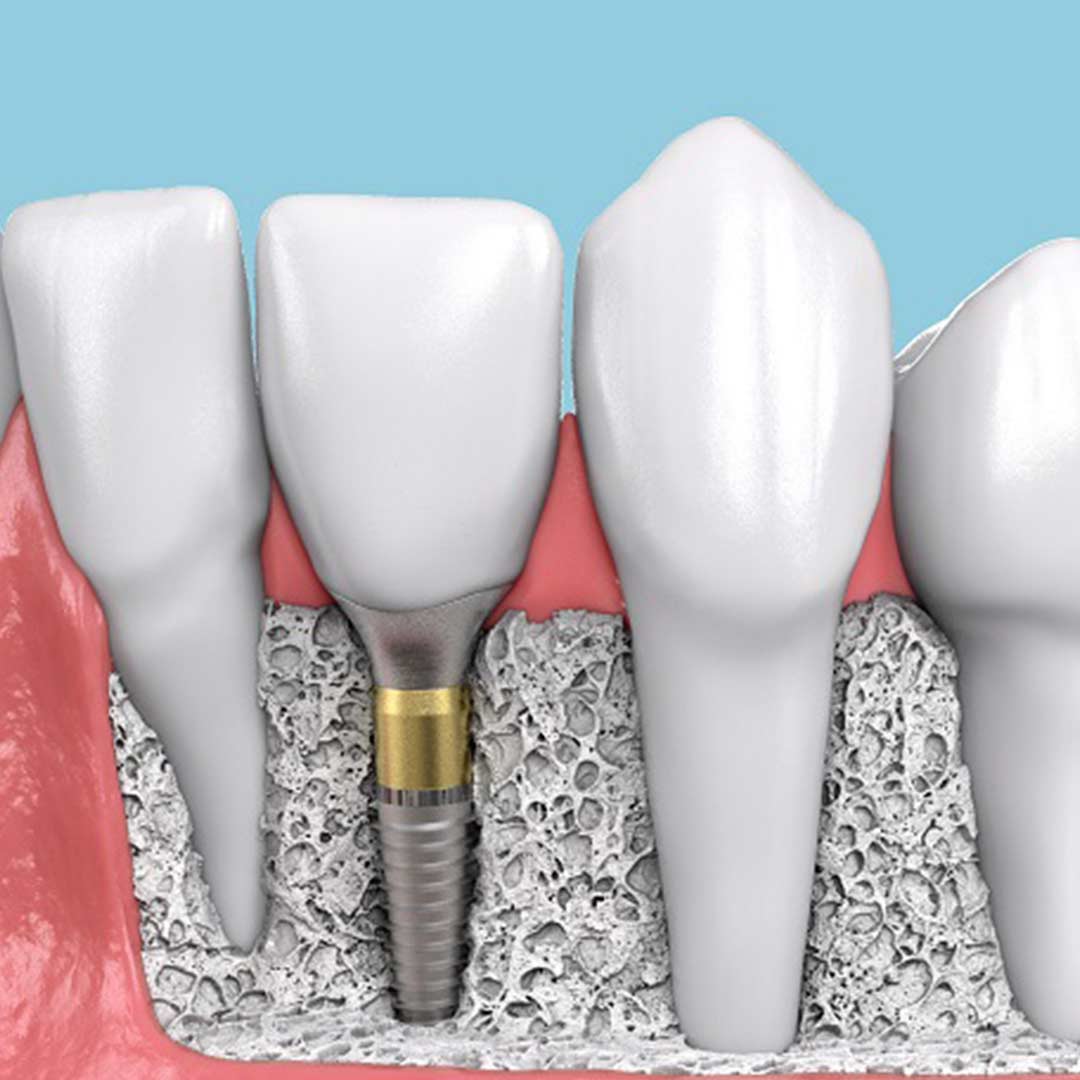

Современные коронки на зубные импланты: виды и фото-примеры